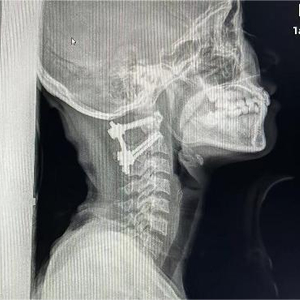

两个小时过去,疼痛不但没有缓解,还越来越厉害。她当即来到暨南大学附属第六医院(东莞市东部中心医院)脊柱外科就诊,做了颈椎X光后,结果令人大吃一惊:这不是简单的“落枕”,而是寰枢关节脱位III型。

寰枢关节脱位又称为寰枢椎脱位,是指颈椎的第一节(寰椎)、第二节(枢椎)之间的关节失去正常的对合关系。这是一种少见但严重的疾病,会引起延髓、高位颈脊髓受压,严重者致四肢瘫痪,甚至呼吸衰竭而死亡。

医生建议她马上住院治疗。入院后,主管医生立即帮她完善颈椎MRI,确认其寰枢椎脱位是由于横韧带断裂引起,予以枕颌带牵引治疗,恢复了寰枢关节正确解剖位置。同时,向上级医生汇报病情。

暨南大学附属第六医院(东莞市东部中心医院)副院长焦根龙博士是脊柱外科学科带头人,他查看了影像学资料、听取汇报后,判断晓娟应择期行手术治疗固定脱位的寰枢椎,不然可能再次脱位。

10月11日一早,在焦根龙带领下,手术室、麻醉科通力配合,全程实施神经电生理监测,脊柱外科团队成功为晓娟实施了寰枢椎脱位切开复位内固定植骨融合术,手术非常顺利,彻底消除了隐患。